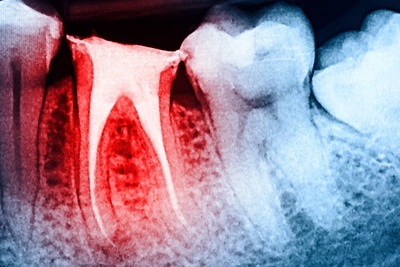

L' Odontoiatria Conservativa L’odontoiatria conservativa è una branca dell’odontoiatria che si occupa del trattamento e della cura del dente compromesso da carie, delle procedure per la loro eliminazione e di quelle relative alla chiusura delle cavità dovuta alla rimozione dello smalto o della dentina cariata. |

Le carie possono essere superficiali o profonde: nel primo caso, il medico dentista si limita ad asportare la dentina e lo smalto interessati, mentre nel secondo può essere coinvolta anche la polpa (con le fibre nervose) e quindi può essere necessario ricorrere alla devitalizzazione.

La devitalizzazione è un’operazione mediante cui viene asportata la polpa dentale, eseguita da specialisti della chirurgia endodontica.

L’odontoiatria conservativa, dunque, come suggerisce il termine, si basa sul concetto della minima invasività: negli ultimi anni sono stati quasi completamente abbandonati gli amalgami d’argento, utilizzati un tempo per otturare i denti, a favore dei compositi, che richiedono un’operazione decisamente meno estesa.